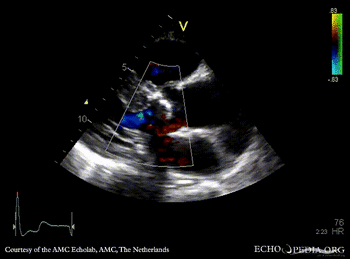

Severe aortic valve stenosis and plaque in abdominal aorta

PSAX: stenosis of aortic valve PLAX with Color Doppler: high velocity transaortic flow, mild aortic regurgitation